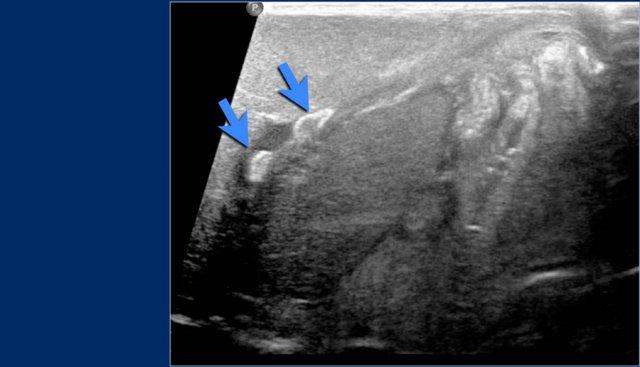

Ở bệnh nhân này, siêu âm phát hiện huyết khối trong tĩnh mạch cửa trái sau khi đặt đường truyền tĩnh mạch rốn (các mũi tên).

Đặt catheter sai vị trí vào tĩnh mạch cửa trái làm tăng nguy cơ huyết khối tĩnh mạch cửa.

Huyết khối tĩnh mạch cửa không có triệu chứng lâm sàng thường gặp liên quan đến đặt catheter tĩnh mạch rốn ở trẻ sơ sinh bệnh nặng, và trong nhiều trường hợp có thể tự thoái triển mà không cần điều trị.